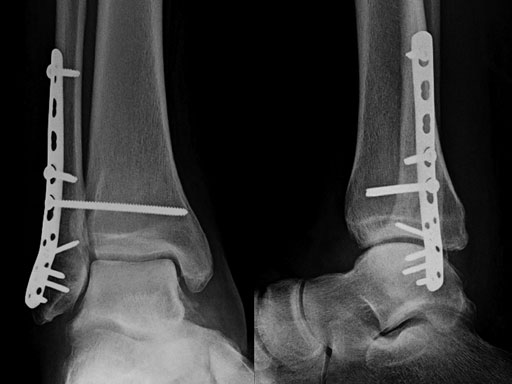

Case provided by Michael J Gardner, St Louis, USA.

A 56-year-old man slipped and fell, sustaining a fracture dislocation of the ankle. His fibula was stabilized with a posterolateral plate. The construct included several nonlocking screws in the diaphysis, and multiple 2.7 mm locking screws in the distal fibula. As with most Weber B fracture patterns, a lag screw was possible from posterior to anterior through the plate. Finally, intraoperatively the patient was found to have a syndesmotic injury, and after reduction, a syndesmotic screw was placed through the plate.